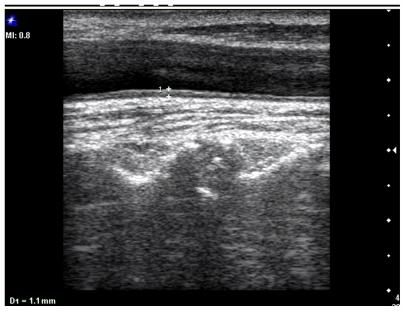

We examined 84 consecutive middle-aged (under 45 years) patients with NAFLD and 65 control subjects matched for age, gender, and body mass index to determine carotid intima-media thickness (CIMT) and flow-mediated dilatation (FMD) in the brachial artery.

There was a statistically significant difference between CIMT and percentage increase in FMD in the patient group (P = 0.002; r = 0.33) when compared with the control group (P = 0.97; r = 0.005). The mean ± standard deviation CMIT was 0.65 ± 0.09 mm in patients and 0.55 ± 0.07 mm in controls. This difference was statistically significant (P = 0.001). Mean FMD in patients was 6.4% and 15.7% in controls. This difference was statistically significant (P = 0.001).